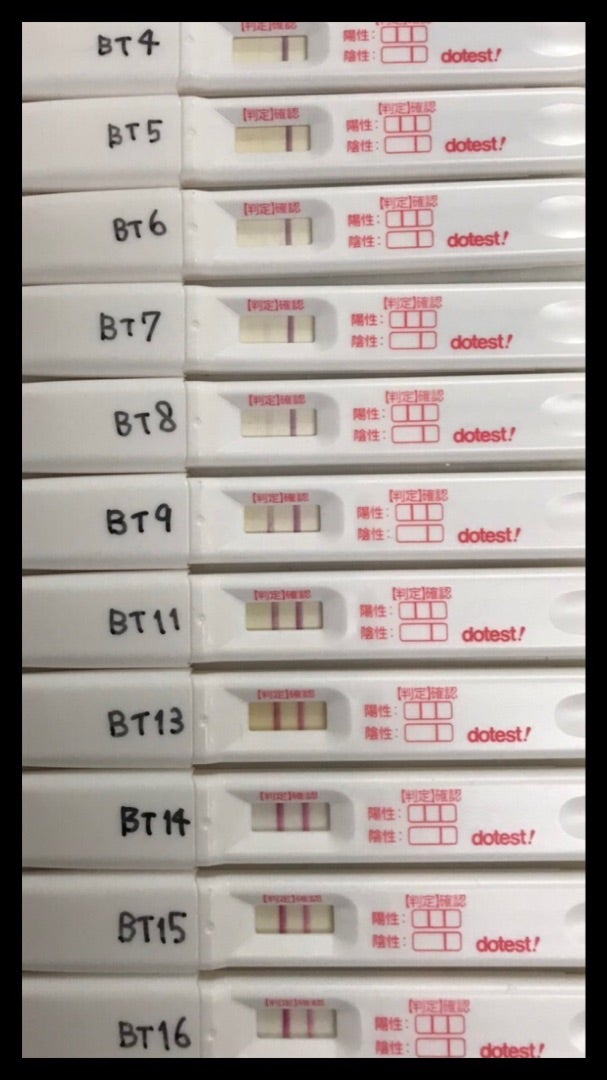

Bt16 5週0日胎嚢確認 妊娠検査薬まとめ Cocoa 37歳 両卵管摘出 2019年8月4度目の移植で妊娠